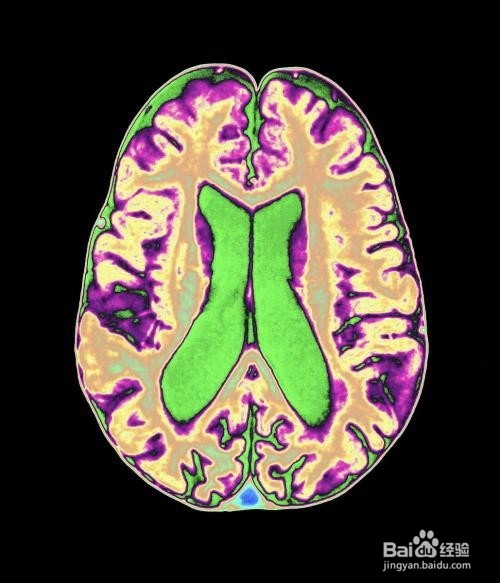

创伤性脑损伤的病因与症状

一般来说,创伤性脑损伤是通过撞击、打击、震荡引起的,或者是一次爆炸对大脑的冲击,又或者是外物穿过大脑。但是并不是说,所有的创伤都会导致创伤性脑损伤,但是一旦发生了,那么就会在一个范围内发生症状(轻度则短暂无意识或者心理状况,重则会长时间无意识,甚至会更严重的是没有思考的能力)。